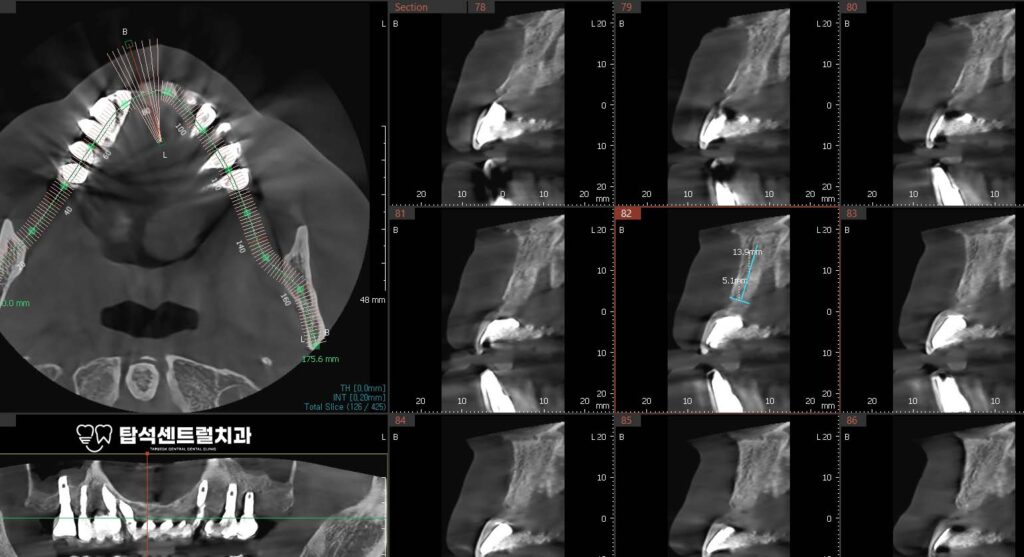

골이식의 역할과 필요성

고정체를 제거한 자리는 잇몸과 치조골이

함몰되기 쉬운 상태가 됩니다.

특히 앞니 부위는 외관상 티가 나기 쉬워

이를 방지하기 위해 광범위한 골이식을 시행합니다.

골이식이란 부족한 뼈를 보충해 주는 시술로

자가골이나 인공뼈 재료를 사용합니다.

새로 심은 부위 주변에도

치조골의 폭을 유지하기 위해

골이식을 함께 진행하는 경우가 많습니다.

뼈가 얇은 부위에서는 광범위하게

이식재를 적용하여 볼륨을 확보합니다.

충분한 뼈의 양과 두께가 확보되어야

임플란트 주위염의 재발 위험을 줄이고

오랜 기간 건강하게 사용할 수 있습니다.

골이식과 임플란트 수술이

잘 진행된 이후로, 수개월에 걸쳐

뼈와 이식재가 단단하게 결합하게 됩니다.